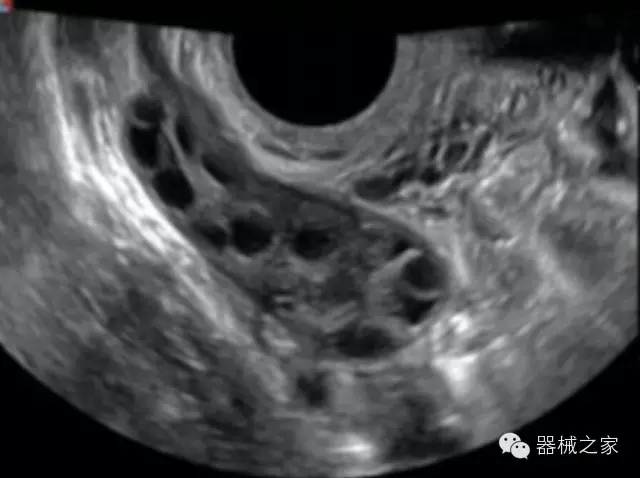

臨床圖片賞析

·完整的3D/4D臨床應(yīng)用,STIC, MCUT 和Auto NT等滿足產(chǎn)科所有應(yīng)用;

·更高的HQ羊膜腔鏡成像技術(shù)精細(xì)觀察每一個(gè)暗區(qū)細(xì)節(jié);

·高效3D/4D成像技術(shù):高速的4D幀頻,豐富的3D成像模式,智能斷層切片功能;